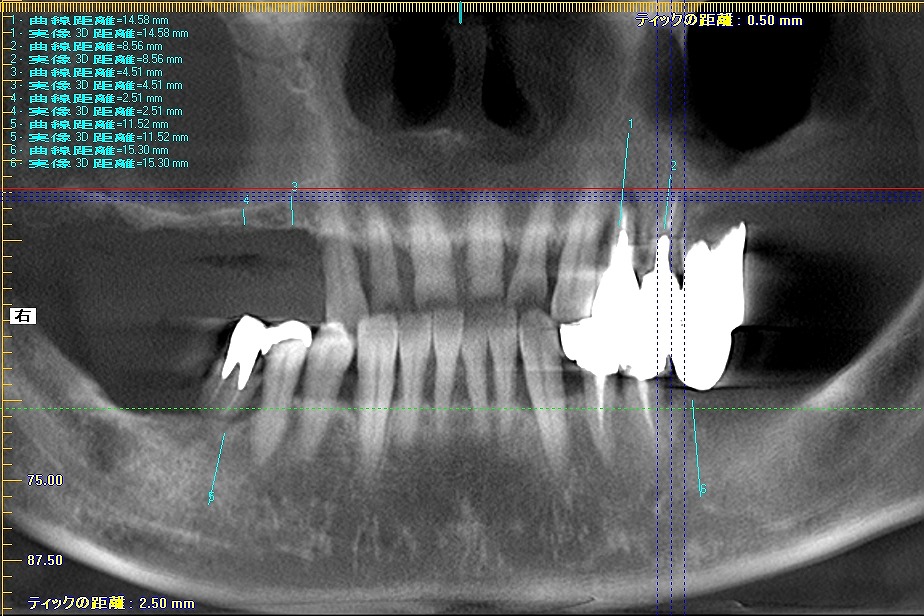

術前のパノラマになります